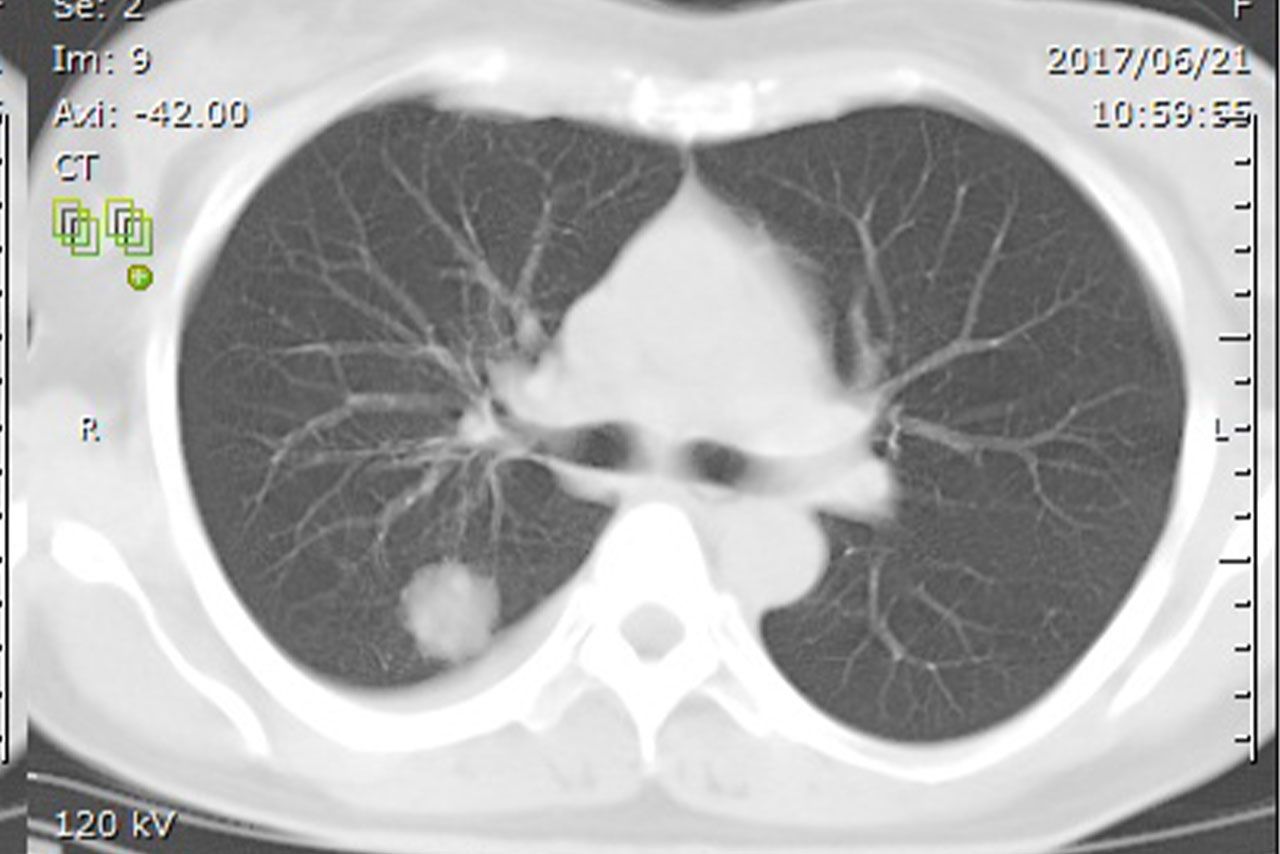

松本みゆきさんが見ても、すぐに「肺がんだ」とわかったというCT画像。白い影がはっきりと写り込む